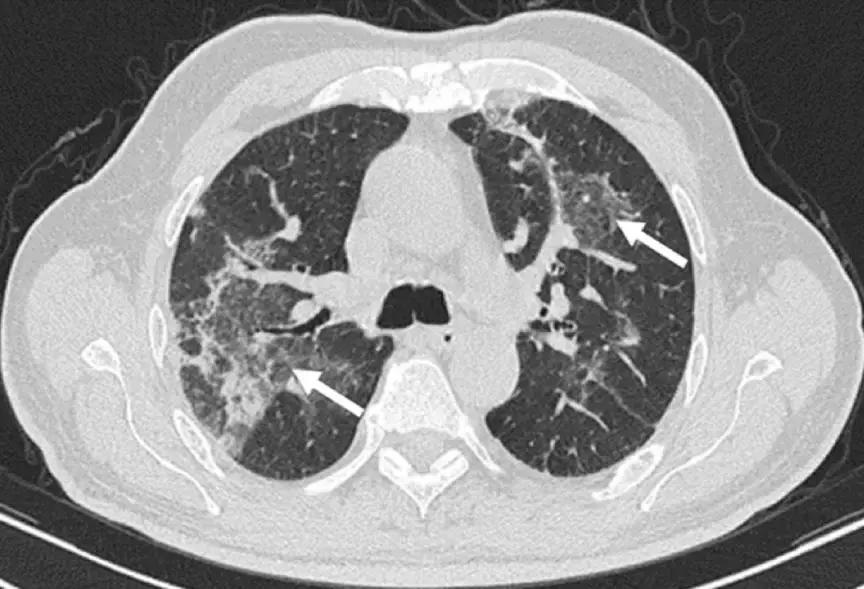

2、影像学是诊断线索

OP的影像表现:实变(周围、沿支气管血管束):80~95%;磨玻璃影:60~90%;小叶间隔增厚:55%;「反晕征」:20%;结节或团块:15~50%;还有「游走性」的特点。

实变:

中心型

混合型

磨玻璃影:

GGO合并带状实变

GGO,合并周围型及带状实变

小叶间隔增厚:

小叶间隔增厚,伴中心型实变、GGO

反晕征:

结节或团块(需要和肿瘤鉴别):